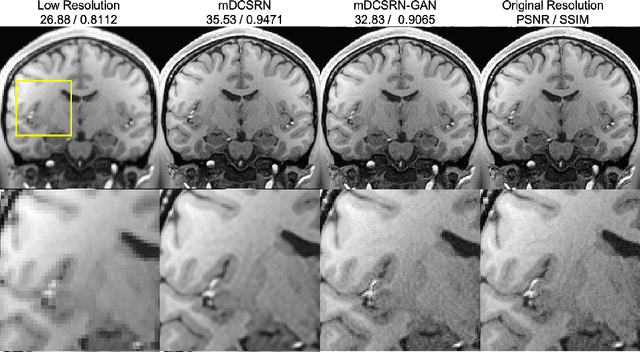

Abstract:High-resolution (HR) magnetic resonance imaging (MRI) provides detailed anatomical information that is critical for diagnosis in the clinical application. However, HR MRI typically comes at the cost of long scan time, small spatial coverage, and low signal-to-noise ratio (SNR). Recent studies showed that with a deep convolutional neural network (CNN), HR generic images could be recovered from low-resolution (LR) inputs via single image super-resolution (SISR) approaches. Additionally, previous works have shown that a deep 3D CNN can generate high-quality SR MRIs by using learned image priors. However, 3D CNN with deep structures, have a large number of parameters and are computationally expensive. In this paper, we propose a novel 3D CNN architecture, namely a multi-level densely connected super-resolution network (mDCSRN), which is light-weight, fast and accurate. We also show that with the generative adversarial network (GAN)-guided training, the mDCSRN-GAN provides appealing sharp SR images with rich texture details that are highly comparable with the referenced HR images. Our results from experiments on a large public dataset with 1,113 subjects showed that this new architecture outperformed other popular deep learning methods in recovering 4x resolution-downgraded images in both quality and speed.

Abstract:High-resolution (HR) magnetic resonance images (MRI) provide detailed anatomical information important for clinical application and quantitative image analysis. However, HR MRI conventionally comes at the cost of longer scan time, smaller spatial coverage, and lower signal-to-noise ratio (SNR). Recent studies have shown that single image super-resolution (SISR), a technique to recover HR details from one single low-resolution (LR) input image, could provide high-quality image details with the help of advanced deep convolutional neural networks (CNN). However, deep neural networks consume memory heavily and run slowly, especially in 3D settings. In this paper, we propose a novel 3D neural network design, namely a multi-level densely connected super-resolution network (mDCSRN) with generative adversarial network (GAN)-guided training. The mDCSRN quickly trains and inferences and the GAN promotes realistic output hardly distinguishable from original HR images. Our results from experiments on a dataset with 1,113 subjects show that our new architecture beats other popular deep learning methods in recovering 4x resolution-downgraded im-ages and runs 6x faster.